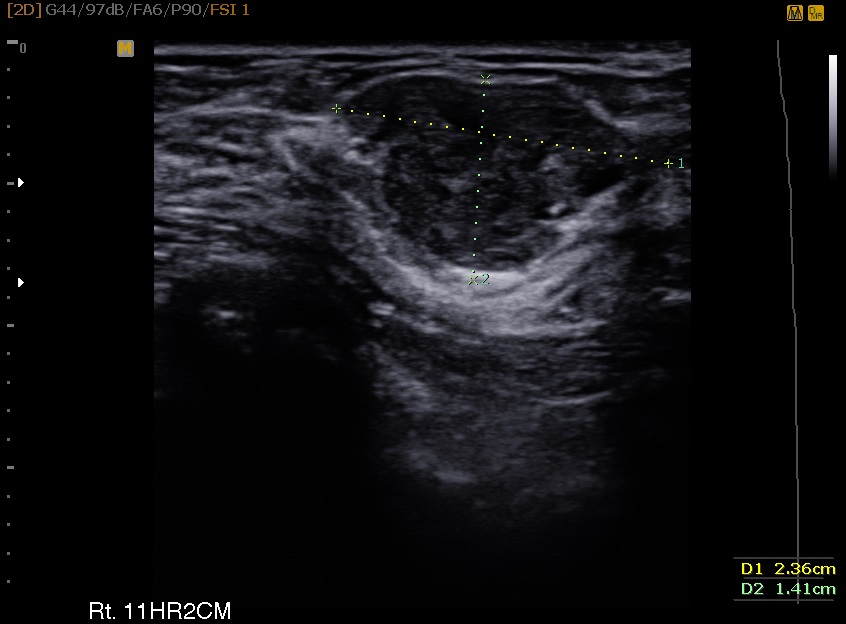

29¼¼ ¿©¼ºÀ¸·Î ¿ìÃø À¯¹æ¿¡ ¸¸Á®Áö´Â ȤÀ¸·Î ³»¿øÇÏ¿© Á¶Á÷°Ë»ç ½ÃÇàÇÏ¿´°í Á¶Á÷°Ë»ç °á°ú ¼¶À¯¼±Á¾ Áø´ÜµÇ¾úÀ¸¸ç ȯÀÚ ¿øÇϼż­ ¸¾¸ðÅè ¼ö¼ú ½ÃÇàÇÏ¿´½À´Ï´Ù.